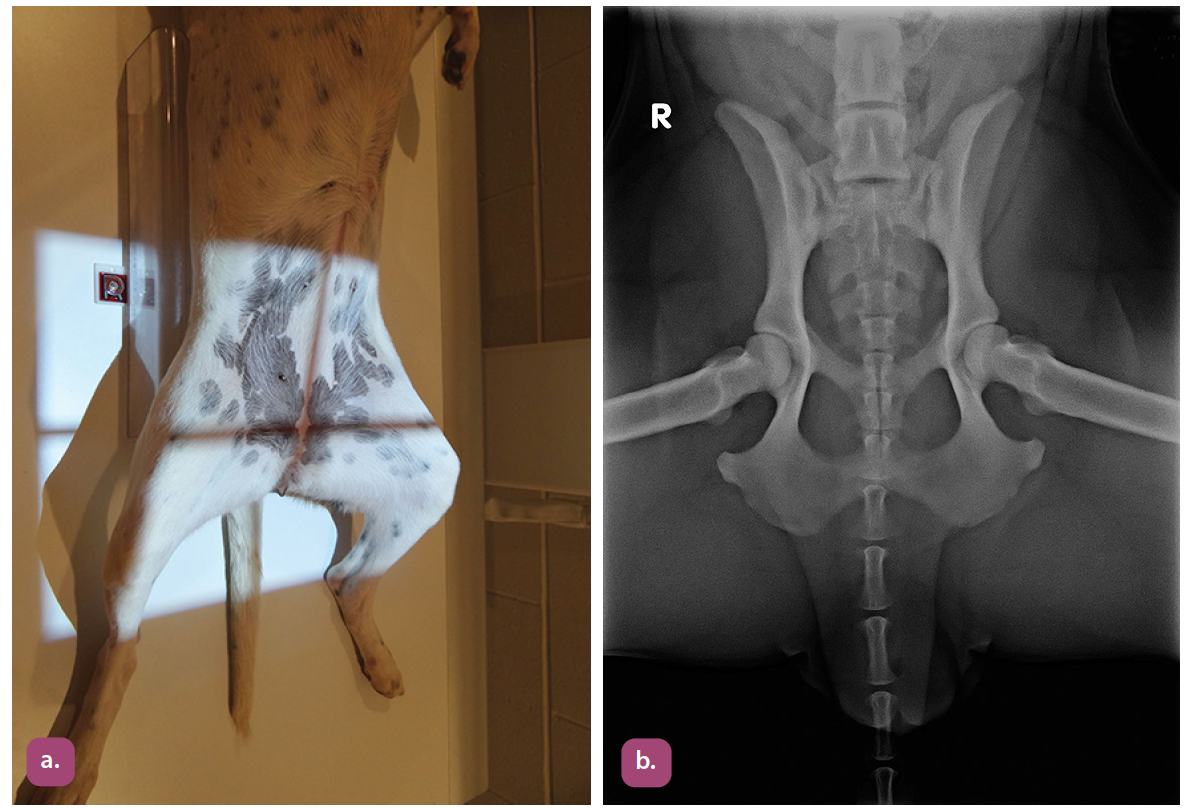

lateral projection of the pelvis

ventrodorsal extended hip projection

ventrodorsal frog leg projection